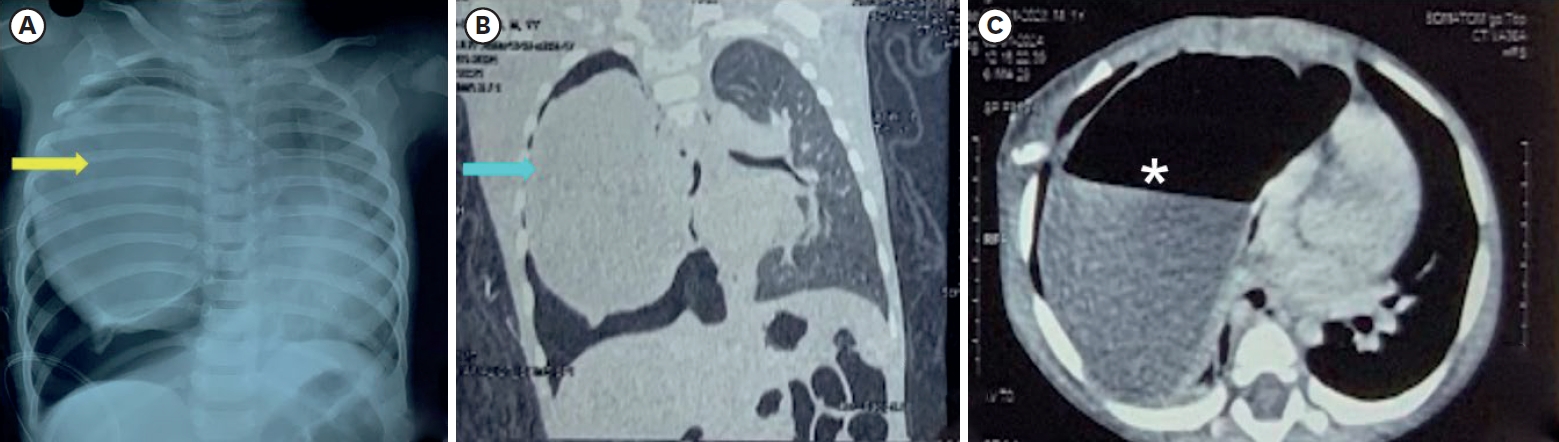

Intrapulmonary Bronchogenic Cyst in an Infant: Rare Presentation and Insights From Literature

Ramyasree Bade, Shailesh Solanki, Shivani Dogra, Nitin James Peters, Jai Kumar Mahajan

Adv Pediatr Surg 2025;31(2):87-92.   Published online December 24, 2025

DOI: https://doi.org/10.13029/aps.2025.31.2.87

Intrapulmonary bronchogenic cysts are rare congenital anomalies that often present diagnostic and management challenges due to nonspecific symptoms. We report a one-year-old female with progressive respiratory distress who was initially misdiagnosed with pneumothorax. Imaging revealed a large intrapulmonary cyst, and surgical excision confirmed the diagnosis. Early intervention ensured a favorable outcome, with no recurrence in one year. This case highlights the importance of considering bronchogenic cysts in pediatric respiratory distress and emphasizes the value of timely surgical management.